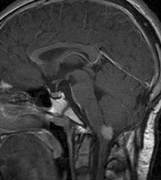

syndrome in 1926. The term von Hippel-Lindau syndrome (VHL) was

first used in 1936.166 The first major clinical criteria for the syndrome were proposed in 1964.167 The main manifestations of von Hippel-Linau syndrome are: histologically similar hemangiomas of the retina and CNS, renal cysts, renal cell carcinomas, pancreatic cysts, pheochromocytomas, and endolymphatic sac tumors.13 EPIDEMIOLOGY The prevalence of VHL syndrome is about 1 in 35,000 to 40,000.168 It is autosomal dominant with greater than 95% penetrance by age 60 years.169 Its expression, even within the same family, may be quite variable, especially for renal disease and pheochromocytoma.170,171 SYSTEMIC FEATURES Cutaneous Findings Cutaneous findings are not part of the diagnostic criteria for VHL syndrome. Neurologic Findings CNS hemangiomas are the most common tumor of VHL, affecting 60% to 80%, with a predilection for the cerebellum and spinal chord. An enlarging cystic component is a frequent finding in symptomatic tumors. Patients typically present in their early 30s; headaches or neck pain in affected individuals should not be ignored.172,173 On microscopy, CNS hemangiomas resemble retinal capillary hemangiomas. Their malignant potential is low.174 The treatment is surgical (Fig. 17, A and B).13 Endolymphatic sac cystadenomas are a sensitive marker of VHL. Patients may present with hearing loss, tinnitus, disequilibrium or facial nerve palsy.175,176 Visceral Findings KIDNEY. Renal cysts are often asymptomatic and do not require treatment. However, complex cysts may carry a risk for malignant transformation. Renal carcinoma affects about a third of patients. Patients typically present in their late 30s. These tumors may be completely asymptomatic, underscoring the necessity for ultrasound screening.13,177 ADRENALS. Pheochromocytomas are benign neural crest tumors of the adrenal medulla (chromaffin cell derived) and probably affect 10% to 20% of patients. Mean age at diagnosis is at about 30 years of age. Pheochromocytomas may be multiple and bilateral. They are catecholamine-secreting tumors that classically produce severe hypertension and anxiety attacks, but they may also be asymptomaic.178 The National Cancer Institute classification of VHL syndrome is in part based on the absence (type I) or presence (type II) of pheochromocytoma (Table 5).171